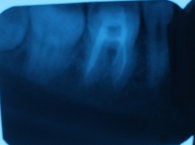

На каких зубах существует вероятность пульпита? 2. Есть ли вероятность, что на снимке присутствуют зубы, такие, что зуб значительно разрушен (от четырёх поверхностей), поэтому здесь требуется восстановление. То есть речь идёт о ситуации кариеса, когда пострадало более трёх поверхностей. Как известно, любой зуб имеет пять поверхностей (1. С внешней стороны. 2. С внутренней стороны (со стороны языка). 3. Со стороны левого соседнего зуба. 4. Со стороны правого соседнего зуба. 5. С жевательной стороны. Я понимаю, что точно диагноз нельзя поставить только по снимку, потому что нужен и визуальный осмотр, но речь идёт просто о возможности (подозрительных зубах и наиболее сложных).

Прям четких пульпитных явлений на снимке я не увидел. Шестой зуб сверху (26), требует установки коронки из-за большого количества пломбы, что по показаниям требуется реставрация вкладкой и коронкой. Не знаю про какой зуб идёт речь, но при разрушении коронковой части зуба более, чем на 50%, необходимо устанавливать коронки. Для более подробной консультации, обратитесь к стоматологу на очный приём.